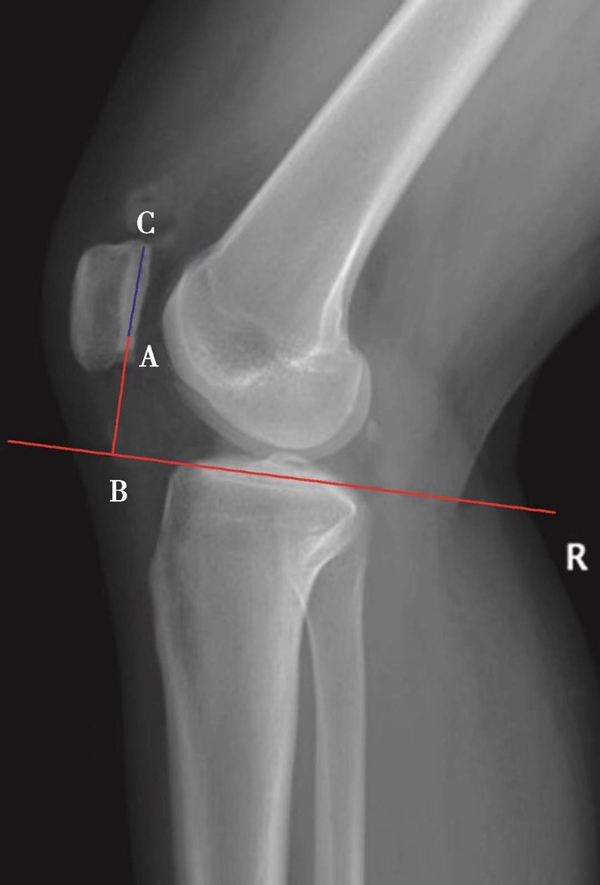

(3)BlackBurne-Peel指数>1.0提示高位髌骨(图8),<0.5提示低位髌骨(图9)。

体位:侧卧位,屈膝无要求。

如图示:AB是髌骨关节面最低点到胫骨平台延长线的垂直距离。AC是髌骨关节面的长度。BlackBurne-Peel指数=AB/AC(图7)。

图7 BlackBurne-Peel指数=AB/AC=0.80,为正常髌骨高度

图8 BlackBurne-Peel指数=AB/AC=1.20,为高位髌骨